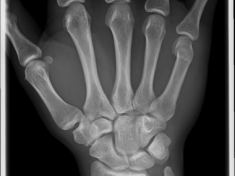

Röntgenbilder